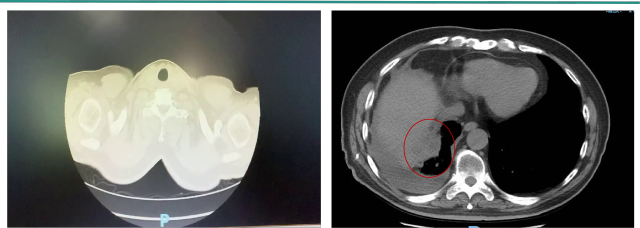

时间:2016-07

诊断:

左肾透明肾细胞癌术后 ,T1aN0M1 IV期 MSKCC分组:低危组

右膈上转移

右侧胸膜转移

右侧胸腔积液